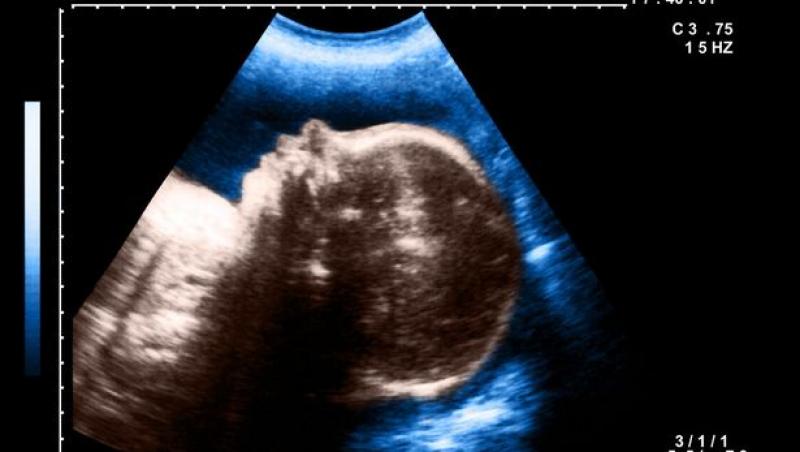

Topul celor mai rare anomalii genetice: de la bebelușul ciclop, la fetița sirenă, adolescentul-lup și tânărul închis într-un circ din cauza figurii înfricoșătoare Topul celor mai rare anomalii genetice: de la bebelușul ciclop, la fetița sirenă, adolescentul-lup și tânărul închis într-un circ din cauza figurii înfricoșătoare